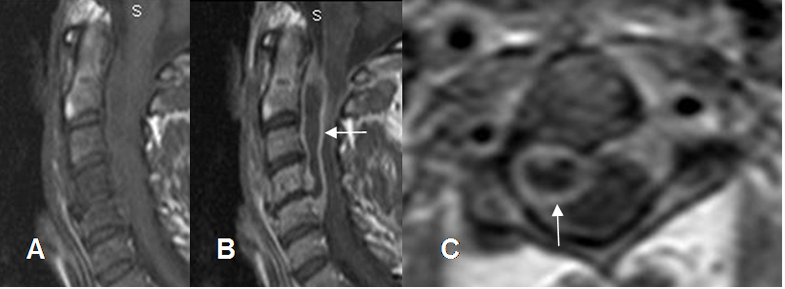

Fig 143 C. Absceso epidural.

A: RM sagital en T1 y B: RM sagital en T2. Igual paciente anterior. Alteración en la señal del arco anterior de C1 y la odontoides, por osteomielitis. (Flechas delgadas). Se encuentra colección epidural por detrás de la odontoides, que comprime la unión craneoespinal. (Flechas gruesas). Además hay hiperintensidad en T2 del bulbo y la medula, por isquemia. (Puntas de flecha).

C: RM sagital en T1 con contraste. Realce del contraste en el complejo C1-C2, los tejidos blandos prevertebrales, los bordes del empiema epidural y las meninges.

Fig 143 D. Absceso epidural.

A: RM axial en T2, B: RM axial en T1 y C: RM axial en T1 con contraste. Igual paciente anterior. Colección epidural que comprime la parte anterior del saco, hiperintensa en T2, hipointensa en T1 y con realce posterior de las meninges, por empiema. (Flecha delgada).